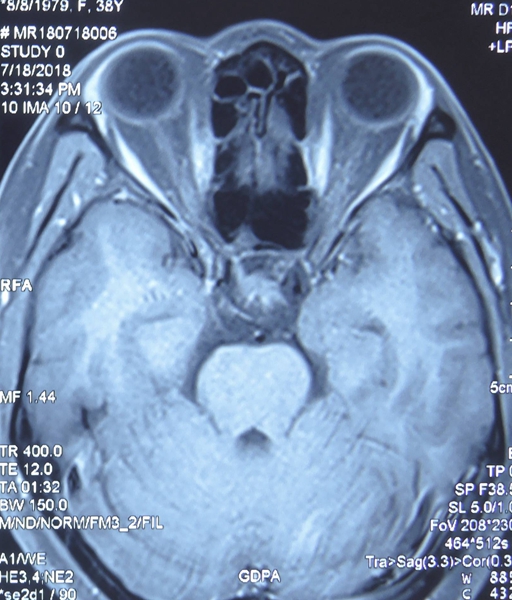

术后,瘤子取净,功能完整保留

手术4个月后,当董女士再次来到湘雅常德医院神经外科病房,一进门叫住了曾照顾过自己的刘冬喜护士长,如焕发新生的董女士一时让护士长竟不能辨认。当董女士说出自己名字时,刘冬喜护士长惊呼,“像换了个人似的!”董女士将复查的结果拿给袁贤瑞教授查看时,袁贤瑞教授非常惊喜,“切得很干净!”

袁贤瑞教授再次为董女士检查,左右眼视力已经从术前的0.1、0.6恢复到0.5、1.2,左眼余光能视物,月经也恢复正常。